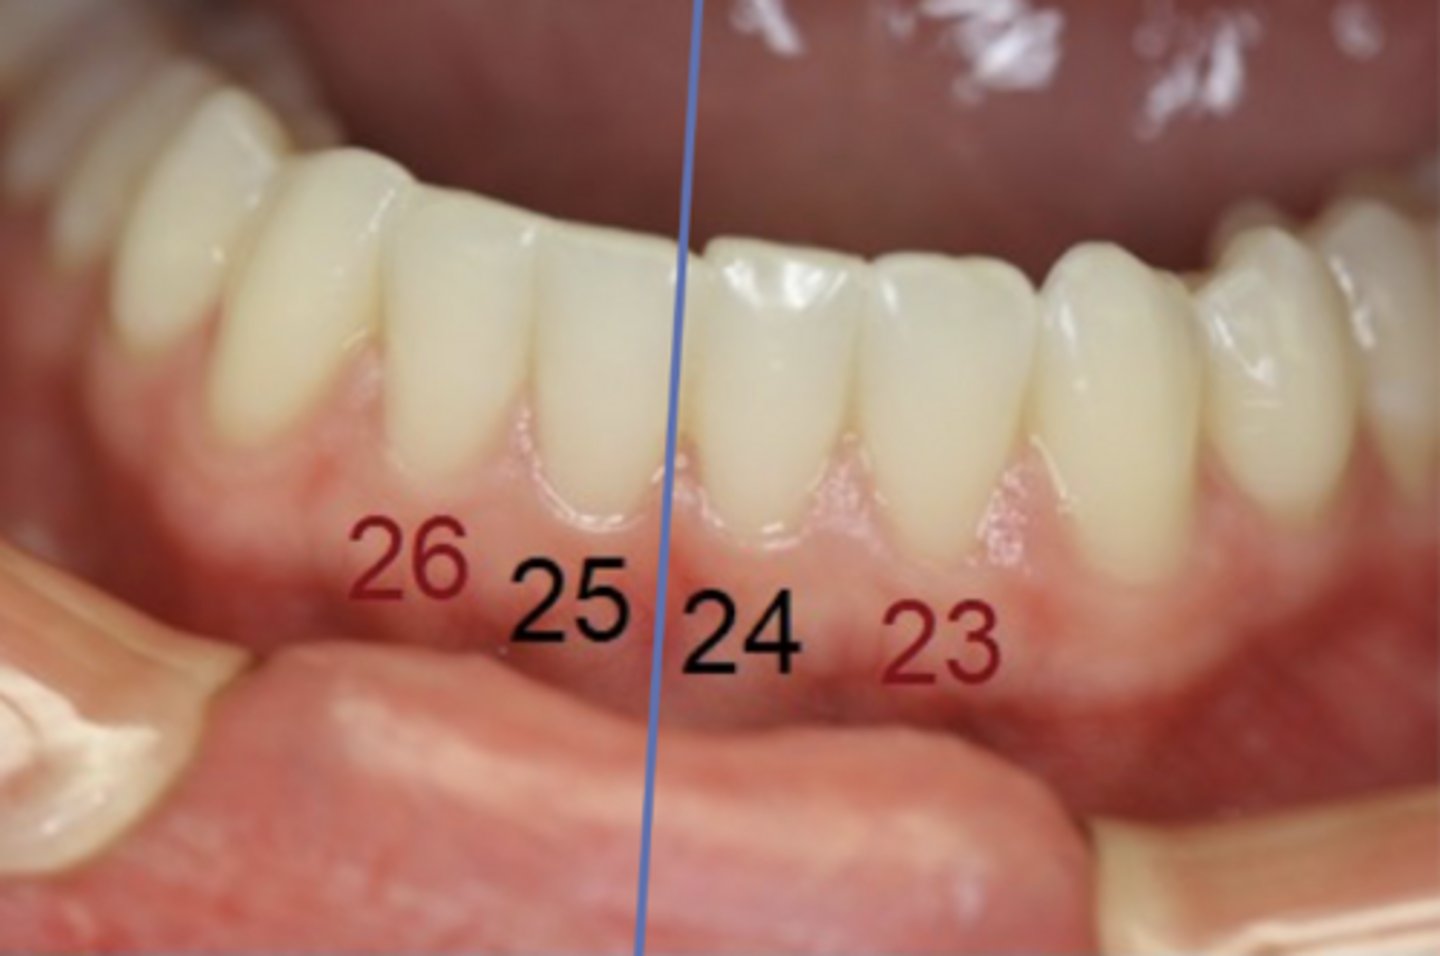

- #24 and #25

...#24 and #25

- #23 and #26